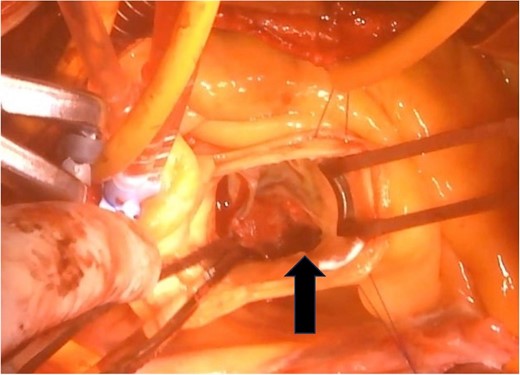

The surgical procedure employed a median sternotomy, with creation of cardiopulmonary bypass via cannulation of the ascending aorta and right atrium. After cross-clamping, cold antegrade cardioplegia was administered. Upon aortic valve exposure, a 2 × 2-cm vegetation was noted on the noncoronary cusp (Figs 2 and 3). The vegetation was quickly removed, and the noncoronary cusp was preserved. Following a 50-min bypass time, with a 35-min cross-clamp time, the patient was successfully weaned off bypass with minimal inotropic support. A portion of the vegetation was sent for culture; however, no bacterial or fungal growth was detected. Further histopathologic examination revealed a fibrin-rich thrombus containing red blood cells with organization at the periphery (Fig. 4).

A 2 × 2-cm vegetation is observed on the noncoronary cusp of the aortic valve.